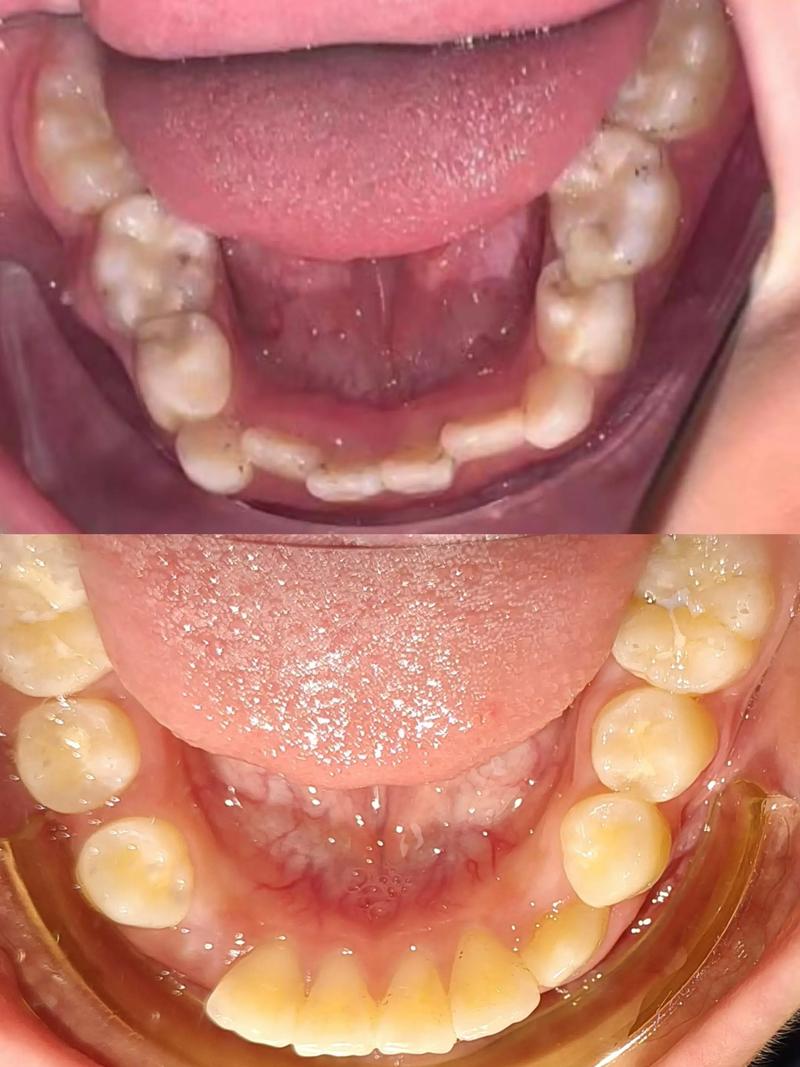

8岁时,孩子大多已萌出上下4颗恒切牙(门牙)和第一恒磨牙(“六龄牙”),可初步判断颌骨发育趋势和牙齿排列问题,若存在反颌(俗称“地包天”)、深覆合(上牙完全覆盖下牙)、牙列严重拥挤、后牙反颌、下巴后缩或前突、长期口呼吸或吭吭(吮指、咬唇等不良习惯),此时干预效果最佳,反颌若不及时纠正,可能导致下颌过度发育、面部凹陷,甚至影响咀嚼功能;而牙列拥挤则可能造成恒牙萌出空间不足,导致“虎牙”等问题。